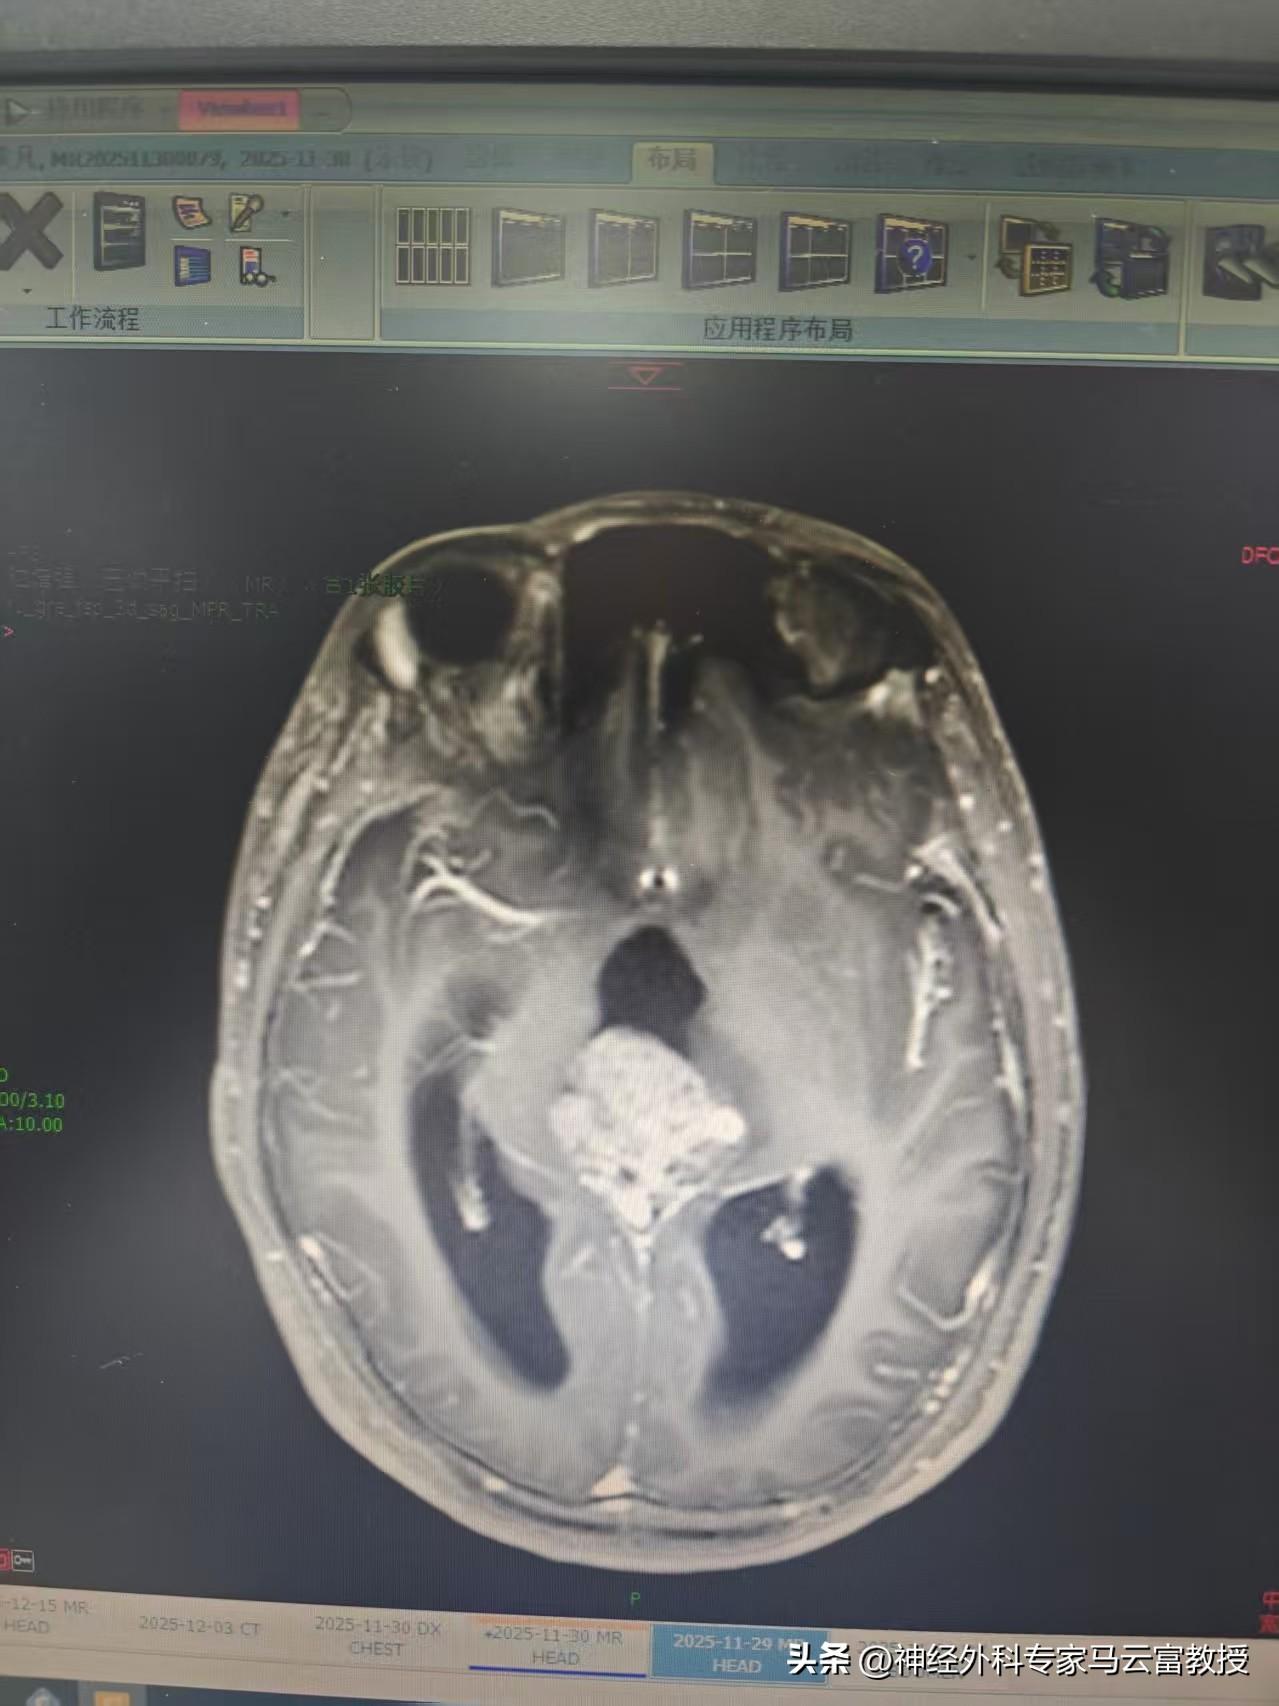

患兒小明(化名)原本活潑健康,近期卻逐漸出現雙眼視力減退,偶有頭暈,並伴有噁心嘔吐。父母察覺異常後,帶其至我院光谷院區就診。經頭顱MR檢查提示:松果體區存在混合信號佔位(考慮生殖細胞腫瘤可能),鄰近背側丘腦受壓水腫,幕上腦室已出現梗阻性腦積水。

腦MRI

腦MRI圖片